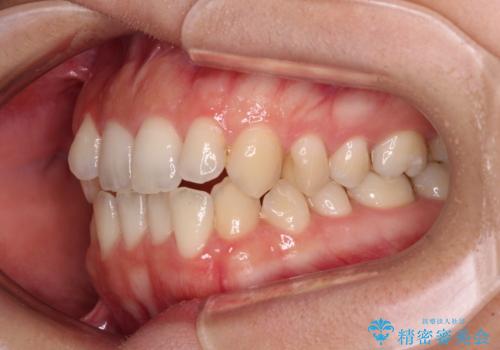

【モニター】オープンバイトをインビザライン矯正で治す

- 前歯の開咬を気にして来院された患者様です。

開咬の治療は、前歯を閉じるように動かすとともに、上下臼歯を圧下(骨内にめり込ませる)させることで進めて行きます。

インビザラインは臼歯の圧下を効果的に行えるため、インビザラインを用いて矯正治療を行うこととしました。

オープンバイトは舌の突出癖により誘発され、治療後も突出癖が残っている容易に後戻りしてしまいます。

治療期間を短縮するためにも、舌突出癖の改善が極めて重要となります。